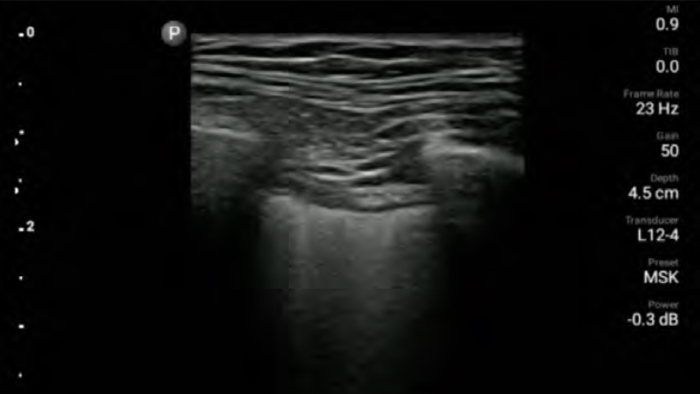

Lumify handheld ultrasound for anesthesiology helps you clearly visualize border definition with your needle placement, surrounding nerves, vessels and fascial planes.

Lumify helps you clearly visualize needle placement, surrounding nerves, vessels and fascial planes.

Broadband linear array transducer

Lumify L12-4 broadband linear array transducer

• 12 to 4 MHz extended operating frequency range

• Aperture size: 34mm

• 2D, steerable color Doppler, M-mode, advancedXRES and multivariate harmonic imaging, SonoCT

• High resolution imaging for shallow applications: soft tissue, vascular, superficial, musculoskeletal and lung

• Center line marker

• USB-C transducer with replaceable cable